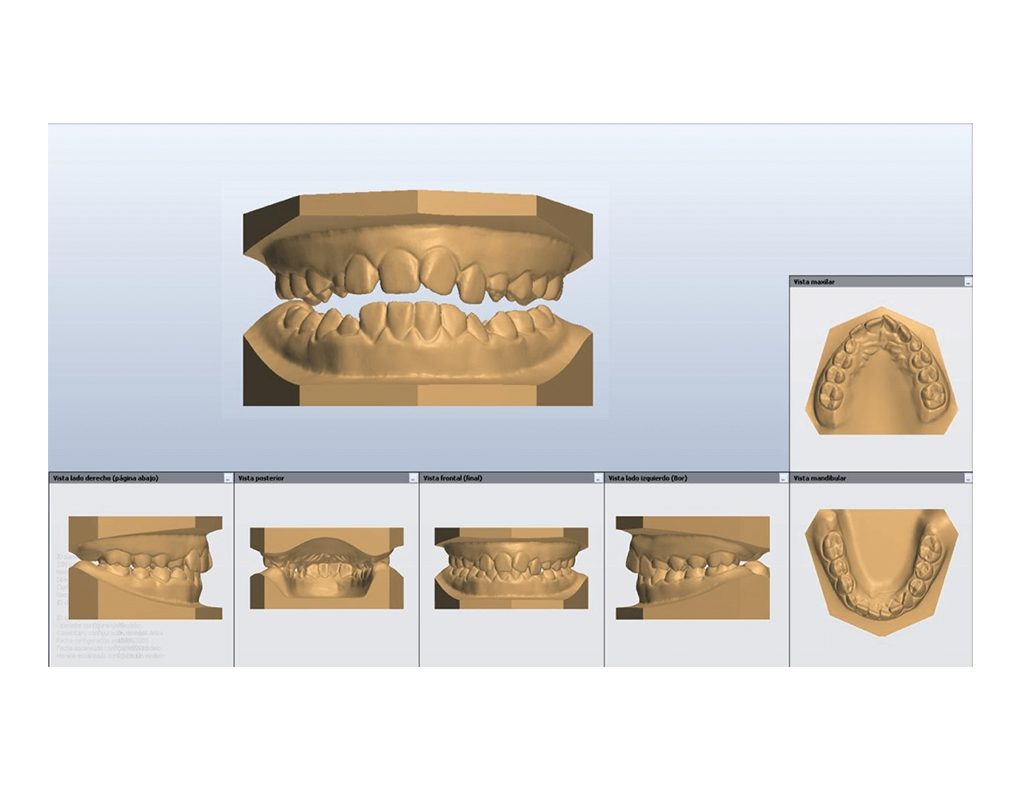

Modelos digitales

Son representaciones virtuales tridimensionales de la boca creadas con escáner intraoral o a partir de modelos ya existentes, trasformando las imágenes en modelos virtuales.